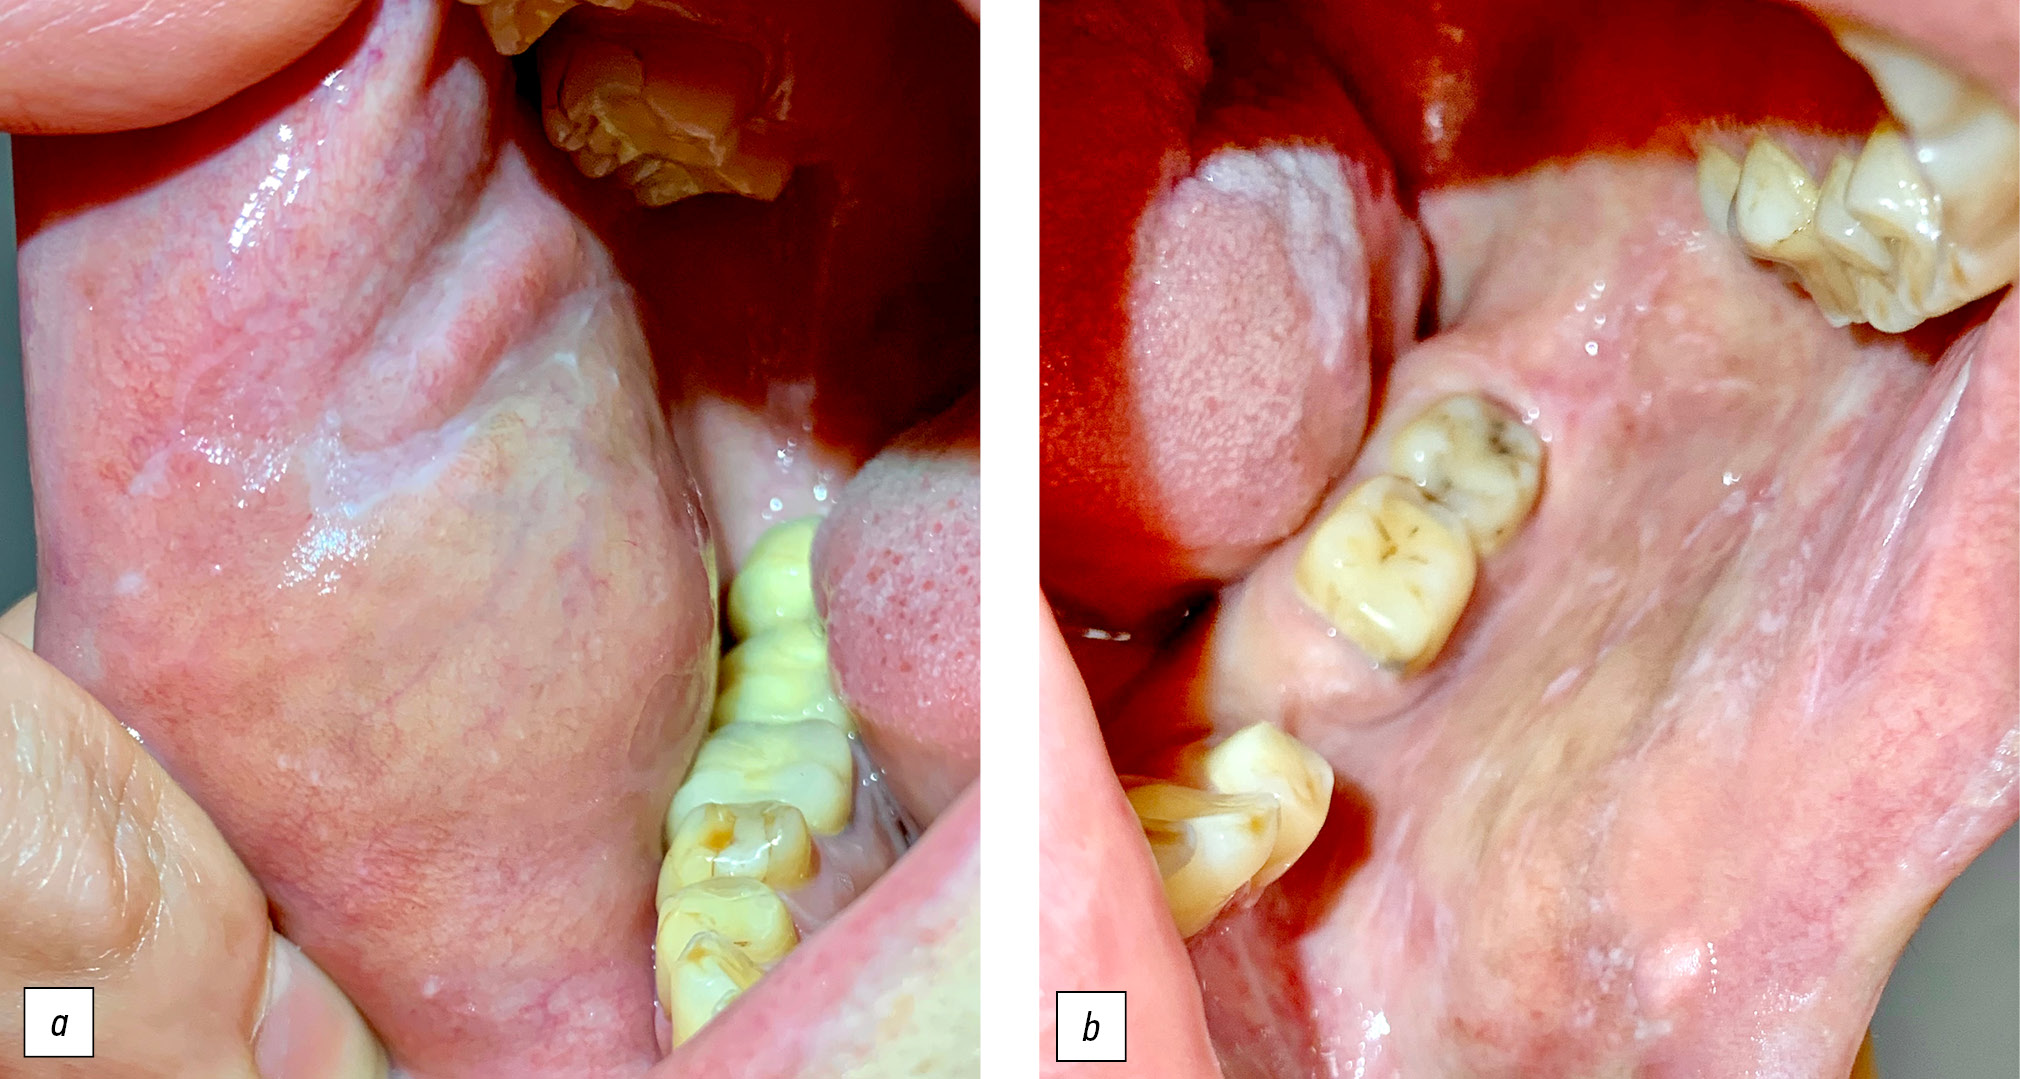

Локальный статус. При осмотре на слизистой оболочке щёк с обеих сторон отмечаются инфильтрированные папулёзные высыпания белого цвета, склонные к слиянию с формированием своеобразной сеточки (рис. 1). Язык складчатый, в средней и задней трети дорсальной его поверхности, а также на боковых участках присутствуют слабо инфильтрированные белесоватые очаги с достаточно чёткими границами. На дорсальной поверхности языка слева отмечается рубец белесовато-розового цвета, длиной около 2,5 см, покрытый незначительным фибринозным налётом. Сосочки вокруг рубца отсутствуют (рис. 2). Субъективно беспокоят незначительная болезненность и онемение языка.

Рис. 1. Больная Л., 45 лет, диагноз красного плоского лишая: на слизистой оболочке щёк с обеих сторон (а, b) отмечаются инфильтрированные папулёзные высыпания белого цвета, склонные к слиянию с формированием своеобразной сеточки.

Fig. 1. Patient L., 45 years old, diagnosis of lichen planus: on the mucous membrane of the cheeks on both sides (a, b) there are infiltrated papular rashes of white color, prone to fusion with the formation of a peculiar mesh.